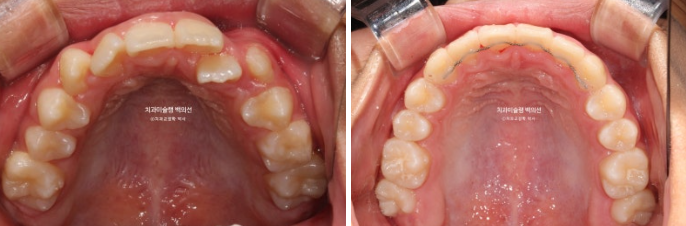

24.02~25.07

24년 1월 교정치료를 위해 온 만 10세 어린이입니다.

24.02

3년 전에 소아치과에서 앞니 부분교정을 한 적이 있다고 합니다.

그래서 위 앞니에는 중절치 두 개를 잇는 철사유지장치가 붙어있었습니다.

중심선이 약 2mm 어긋나 있고 위 앞니 치축은 한쪽으로 기울어져 있습니다.

앞니가 깊게 물리는 과개교합도 보입니다.

공간부족으로 인한 덧니가 심해 반대교합이 있습니다.

어긋난 중심선이 맞아졌으며 기울어진 앞니 치축도 좋아졌습니다.

앞니가 깊게 물리는 과개교합도 좋아졌습니다.